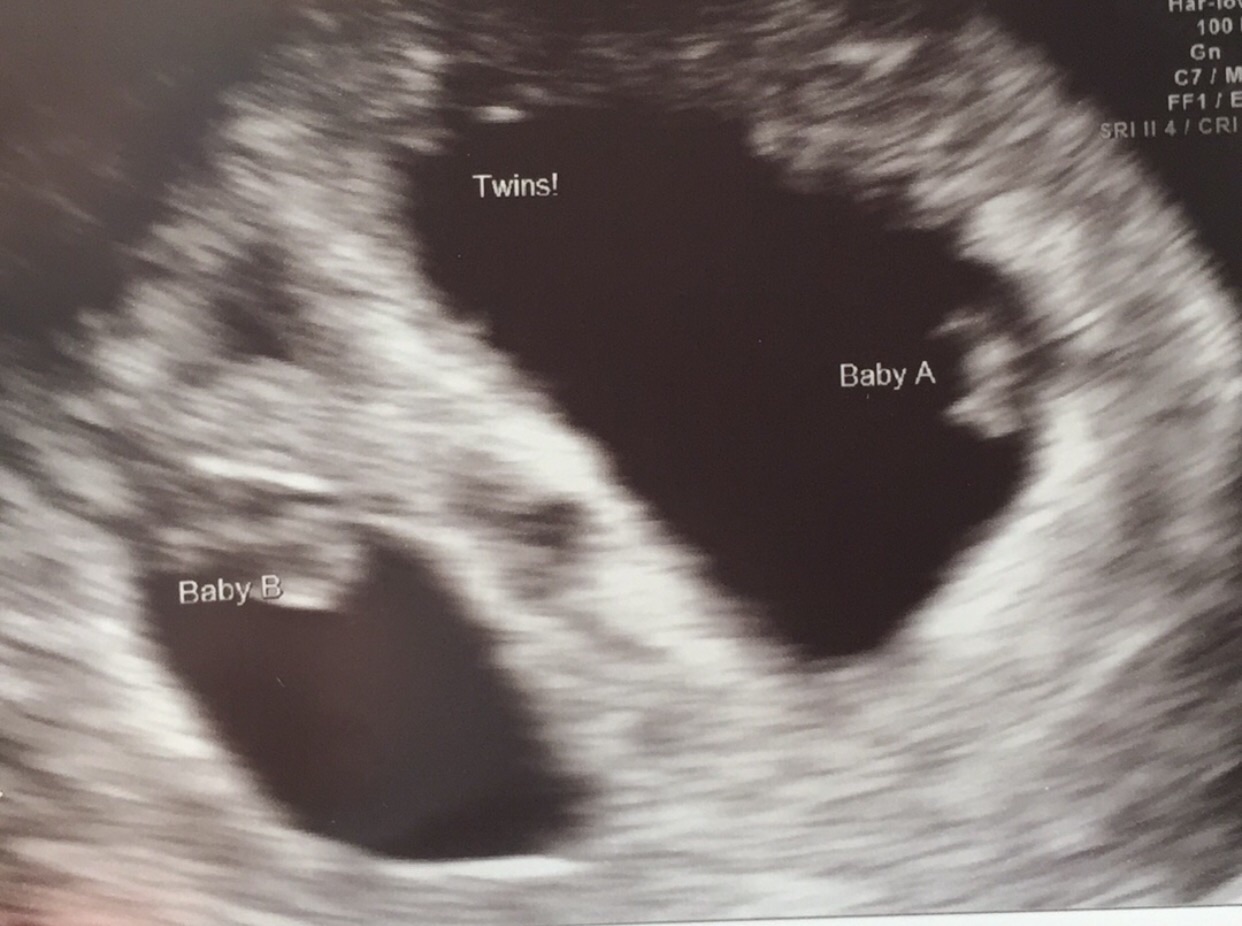

<3 Twins! Our boy and girl coming end of February!  <3

• 13w today, saw perinatologist for the first time and babies are still cooking nicely. He had a little concern on Baby B- something about density/thickness at the back of the neck. Did the MaterniT21 test and will await results. I don't think I will risk an amnio. Will be scheduled for a cerclage sometime soon. Ate and (so far, fingers X) kept down Mexican food today! Weight is stable and I am hydrating on my own still!

Twins, @fuzzbumble! How exciting! Yay!

• Turns out it's twins for us!